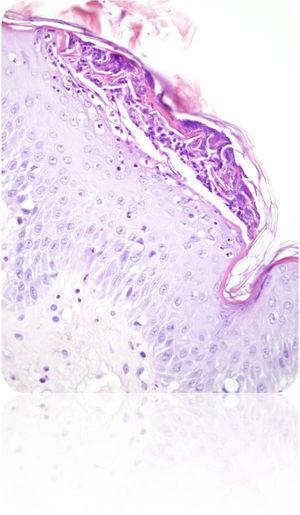

Descripción del casoGestante de 28 semanas, que ingresó por cuadro de lesiones eritematosas generalizadas acompañado de fiebre y malestar general. Como antecedentes presentaba un hipotiroidismo primario autoinmune con tratamiento sustitutivo; aproximadamente 5 años antes presentó una crisis tirotóxica que requirió hospitalización. Durante el ingreso actual, se solicitó valoración a Dermatología por lesiones cutáneas de tipo eritematoso con pequeñas pústulas en forma de placas (figs. 1 y 2), que fueron progresando a pesar del tratamiento tópico corticoideo hasta formar una gran placa preesternal con abundantes pústulas en su periferia, junto con aparición de pequeñas placas eritematosas y pústulas en otras zonas del tórax y el abdomen superior (fig. 3). Se tomaron cultivos y biopsia de las lesiones. Los cultivos fueron informados negativos y en el estudio histológico de la muestra se reveló una epidermis sin hiperplasia llamativa y ortoqueratosis en la mayor parte de la muestra alternando con pequeños focos de paraqueratosis en montículos. Se observaron una discreta espongiosis y la formación de abscesos neutrofílicos en capa superficial de la epidermis y en la capa córnea (microabscesos de Kogoj y Munro, respectivamente) (figs. 4 y 5). En la dermis, se observaron un discreto edema y un infiltrado inflamatorio linfohistiocitario perivascular superficial. Puntualmente, se observaron focos de exocitosis neutrofílica.

El estudio de inmunofluorescencia para detección de IgG, IgM, IgA y C3 resultó negativo. El dato más característico de la biopsia es la presencia de abscesos de Kogoj, que histológicamente se ven también en la enfermedad de Reiter, dermatofitosis pustular, impétigo bacteriano, erupción pustulosa a drogas y candidiasis. Se realizaron técnicas histoquímicas para detección de microorganismos patógenos, siendo negativos el PAS, Groccot y Gram; eran, por tanto, pústulas estériles y se descartó la presencia de hongos.